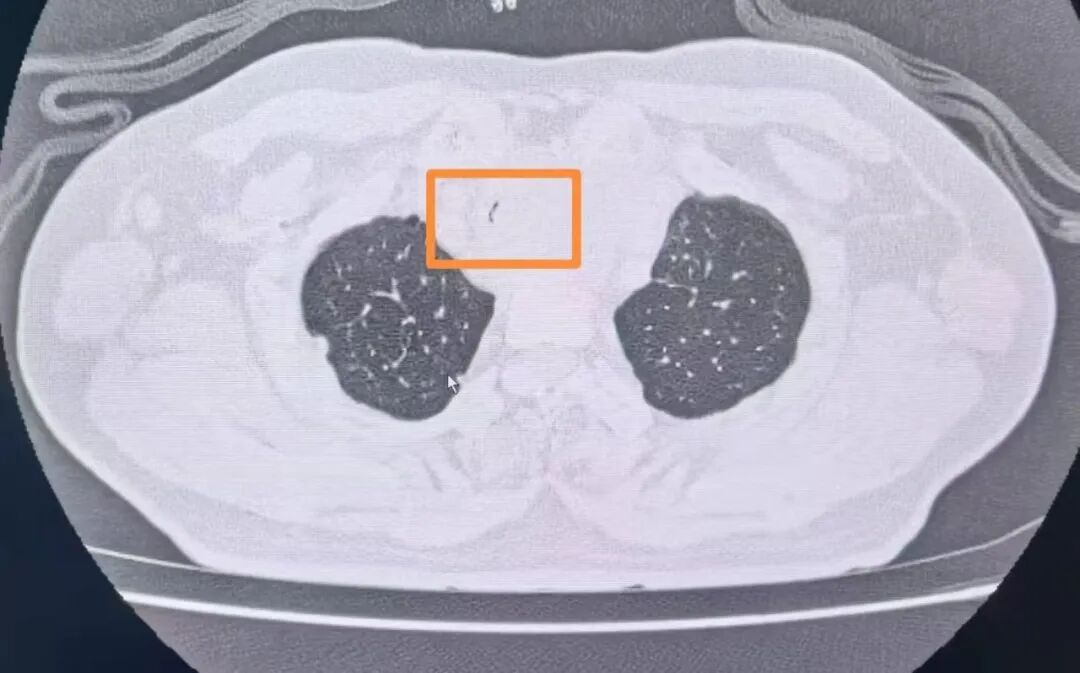

经复查胸部CT发现患者气管已经出现明显狭窄,内径最窄处直径不到2mm(正常成年男性气管内径为18-22mm),呈“一线天”样改变,整个气管仅靠一条细微的缝隙维持着少量的通气,意味着病人随时有发生窒息的危险。甲乳外科立即组织开展了多学科讨论。经过对病情的充分分析,呼吸与危重症医学科副主任陈晖建议紧急行气管内支架置入术解除大气道梗阻。